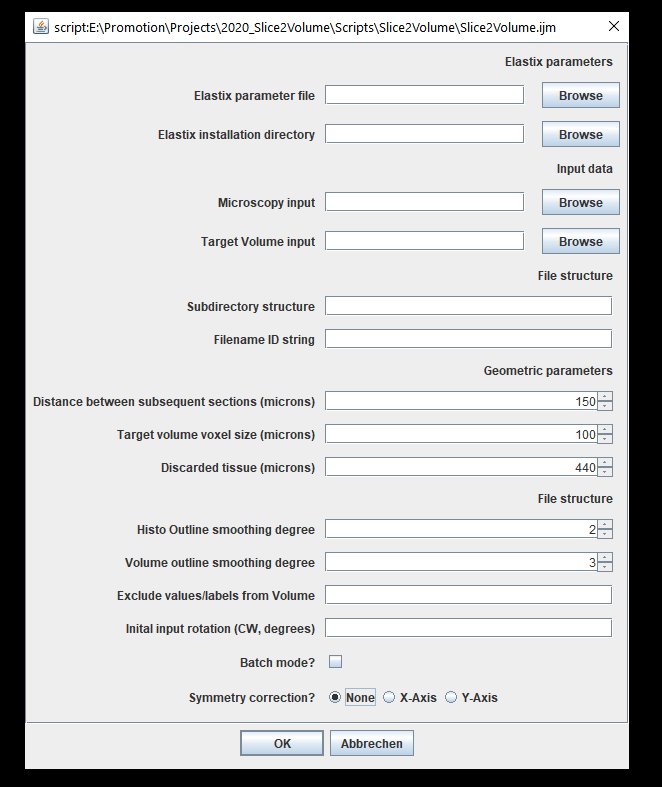

Usage

Now tell us already how to use it! Ok ok...here we go. First download the repository, open the file "Slice2Volume.ijm" in Fiji and click "Run". You'll see this GUI:

|

|---|

| Slice2Volume user interface in Fiji |

I tried to make the script as versatile to different file structures and input data, but there are some necessary parameters to set:

- Elastix parameter file: This should be set to the file "elastix_parameters.txt" in the repository.

- Elastix installation directory: Should be set to the directory tht contains elastix.exe and transformix.exe

- Microscopy input: This should be the root directory that contains all the separate slice data (root in the above example)

- Target volume input: Path to the volumetric brain atlas file (e.g. DSURQE atlas)

- Subdirectory structure: If your slice data has subdirectories (e.g. my_subdirectory in the bove example), put "my_subdirectory/" here.

- Filename ID string: You may have other files in our slice directory; give a string here that identifies the image you would like to register (e.g. "my_image.tif" in the above example)

- Distance between subsequent sections (microns): How far apart are your tissue sections?

- Target volume voxel size? (microns): Should be isotropic, for DSURQE it's 40microns.

- Discarded tissue (microns): How much tissue was cut away from the sample until the sample 0000_Scene_1 was collected?

- Histo outline smoothing degree: The higher this number, the smoother, the lower the more ragged the contour of the histological image will look.

- Volume outline smoothing degree: Same as above, just for the volume image.

- Exclude values/labels from Volume: if you want to remove particular labels (e.g. bulbus) from the volume image, list the corresponding values here, separated with a comma (100,101,102) or with a dash (101, 102, 110 - 120, 130, etc)

- Initial input rotation: If, as shown above, the histological image has a different orientation than the atlas, you can either rotate the atlas or specify a degree (ideally multiple of 90) to rotate the histological image before registration

- Batch mode off: See what's happening!

- Symmetry correction: This is relevant if, for instance your atlas was previously warped to match another data source (MRI, CT, etc). In that case, the atlas may be tilted (see figure below). The registration goes through the volume stack from slice to slice, it is assumed that the orientations match. If the atlas is tilted as shown below, this will not work any more. The symmetry correction provides a way out by rotating the atlas round the specified axis, until it is horizontally symmetrical.